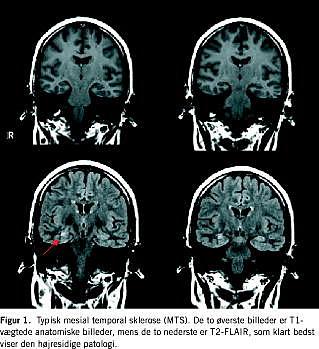

Udviklingen inden for MR har givet en række muligheder for langt hurtigere skanningssekvenser end dem, der var gældende for år tilbage. Det er i den sammenhæng vigtig at gøre sig klart, at ikke alle sekvenser er lige følsomme til påvisning af patologi. Ud fra de fysiske principper for sekvenserne må man umiddelbart antage, at de hurtige har dårligere kontrastfølsomhed og dermed lavere diagnostisk sikkerhed [3]. Dette gælder specielt for de hurtige T2-sekvenser, som mange steder er standard i dag. I udredningen af epilepsipatienter bør man derfor sikre sig, at man ud over hurtige »anatomiske« sekvenser også gør brug af mere tidskrævende kontrastmæssigt potente sekvenser som T2-FLAIR (fluid-attenuated inversion-recovery ) (Figur 1 ). Af hensyn til muligheden for at påvise strukturelle misdannelser er det endvidere vigtigt, at udredningen omfatter en tredimensional optagelse med submillimetertynde snit. Til karakteriseringen af en læsion er det vigtigt, at undersøgelsen omfatter såvel T2- som T1-vægtede sekvenser. Indgift af intravenøs kontrast er normalt kun nødvendig i forbindelse med vurderingen af en påvist tumors differentieringsgrad.